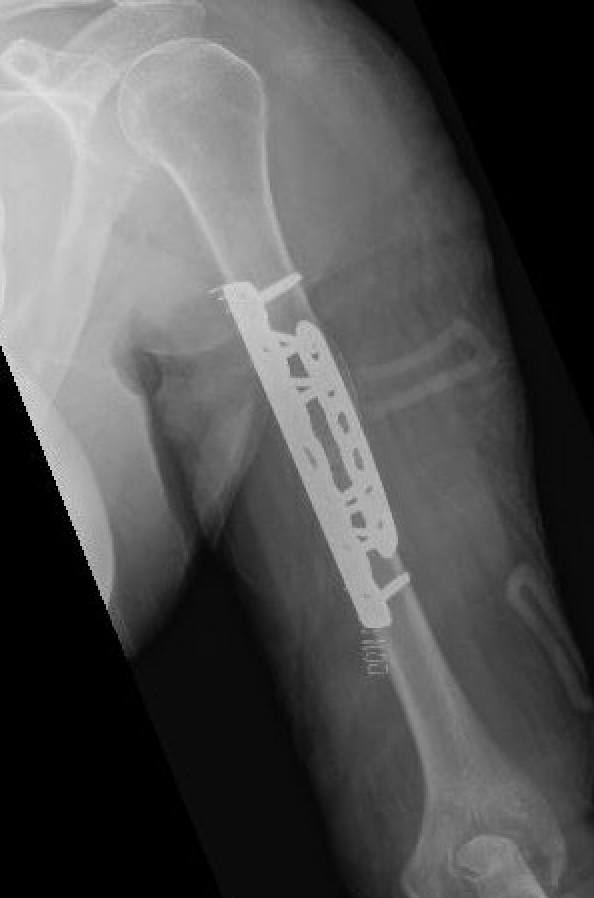

Technique

Approach

- fracture site dependent

- 4.5 mm plate with 6 cortices above and below

- if use 3.5 mm long proximal humeral plate, suggest 8 cortices below

- use iliac crest bone graft

- consider dual plating in proximal fractures with insufficient fixation, or in poor bone quality

Complications of ORIF

Nonunion

Revision of fixation to longer posterior plate